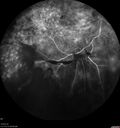

42 year old man (date 2018): Prior to 2 months ago the vision in the right eye was good. This started with a glob in the vision and then the vision got better. Then the string came back down and is getting bigger and bigger. The last time he had bleeding in the left eye he had surgery in 2009. The left eye is now doing OK other than there is a cataract. The right eye had some laser treatment done in 2009. The vitrectomy and laser were done at William Beaumont. VA OD: sc3'/200 NscUnable VA OS: sc20/40 NscJ2-1

PDR and Vitreous hemorrhage - Second FA is following PRP laser265 views42 year old man (date 2018): Prior to 2 months ago the vision in the right eye was good. This started with a glob in the vision and then the vision got better. Then the string came back down and is getting bigger and bigger. The last time he had bleeding in the left eye he had surgery in 2009. The left eye is now doing OK other than there is a cataract. The right eye had some laser treatment done in 2009. The vitrectomy and laser were done at William Beaumont.

VA OD: sc3'/200 NscUnable

VA OS: sc20/40 NscJ2-1